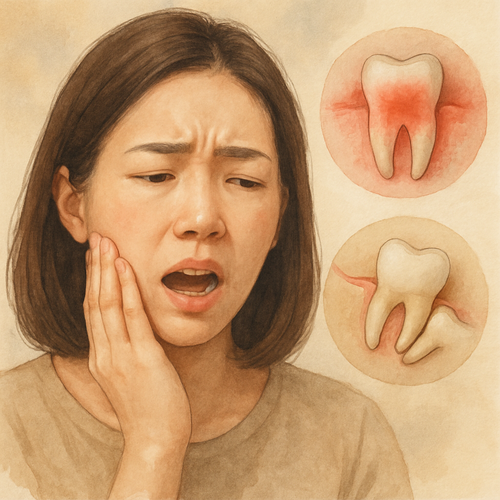

안녕하세요! 어금니 안쪽 잇몸이 욱신거리고 붓는 통증, 혹시 겪어보신 적 있으신가요?

단순한 염증인 줄 알았는데 양치할 때마다 피가 나고, 통증이 반복된다면 치주염이나 사랑니 문제일 수 있어요.

치주염과 사랑니, 두 가지 모두 어금니 안쪽 통증을 유발할 수 있으니 확실하게 구분해 보는 게 중요합니다.

어금니 안쪽 통증은 대표적으로 치주염 또는 사랑니 문제로 인해 발생할 수 있습니다.

두 질환은 증상이 비슷하지만 치료 방법이 완전히 다르기 때문에 정확한 구분이 필수입니다.